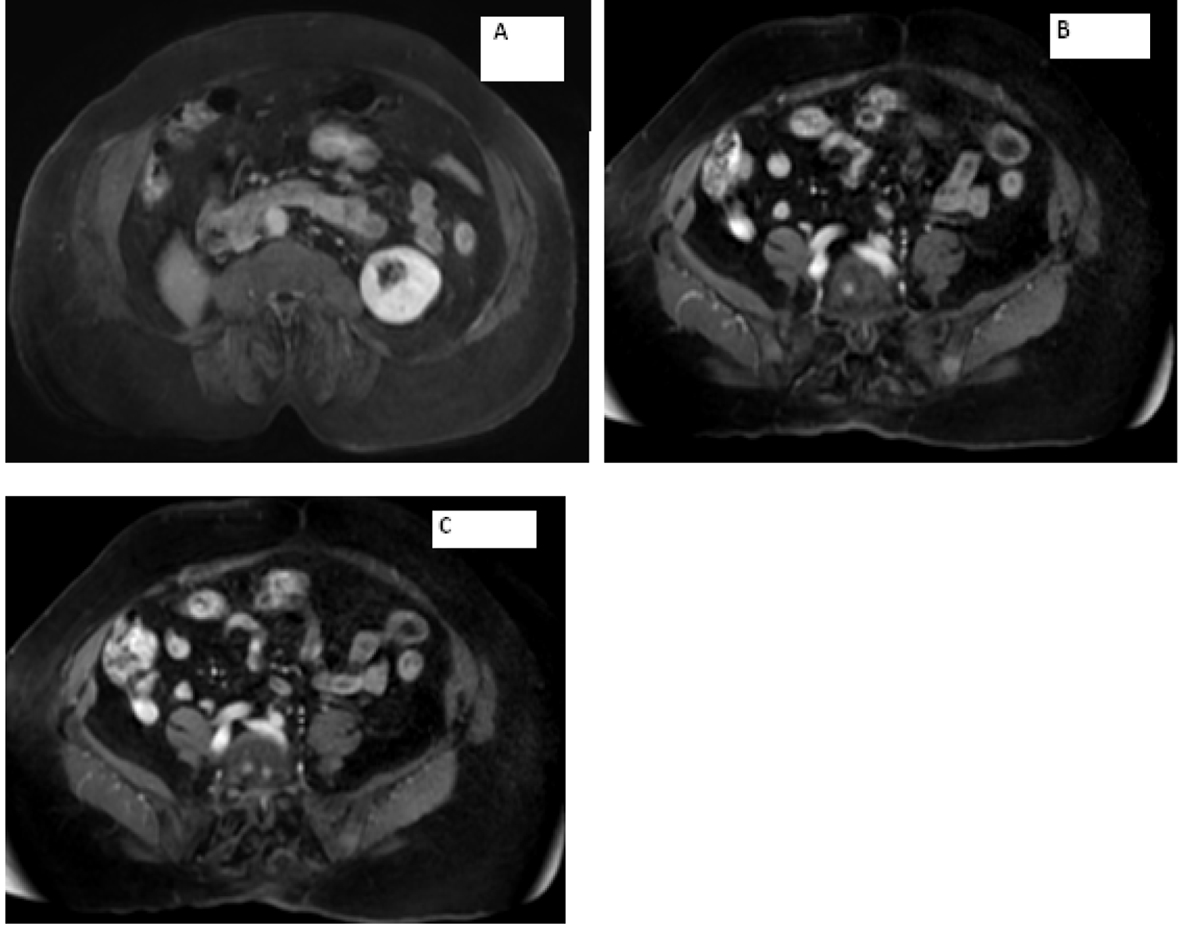

MRI of the spine confirmed bilateral iliac bone metastasis, T-10 diffuse infiltration of metastasis, retroperitoneal lymph nodes and several nodules along the crus of the right diaphragm (Fig. 4). Patient was started on denosumab and zoledronic acid, and she received 10 fractions of radiotherapy to her right hip.

![]() Click for large image | Figure 4. (A) Multilevel-multifocal osseous metastases particularly within thoracolumbar spine with slight epidural extension at T-7 and mild epidural disease at T-10 without cord compression. (B) Right retrocrural/paraspinal metastasis is seen at T-12 and L-1 level measuring about 1.5 cm. |

Computer tomography of the abdomen also showed increased soft tissue nodules in the right adrenal bed with multiple lytic osseous lesions, and distal ileal wall thickening secondary to post radiotherapy changes (Fig. 5).

![]() Click for large image | Figure 5. Multiple predominantly osseous metastasis with metastasis in the right iliac bone, increased conspicuity of several soft tissue nodules in the right adrenalectomy bed consistent with recurrent neoplasm, a superior structure measuring 3.4 × 2.6 cm not well defined from adjacent unopacified liver is seen, the right diaphragmatic crus and the unopacified IVC and an adjacent posterior nodule measuring 3 × 1.6 cm is noted. |